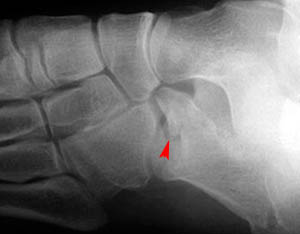

In addition to the anterior and posterior calcaneal fractures shown in the images above, compression and stress fractures of the calcaneus are also common. Look at the two images below showing compression fractures of the calcaneus.

Lateral view

Oblique view

Close-up of lateral view